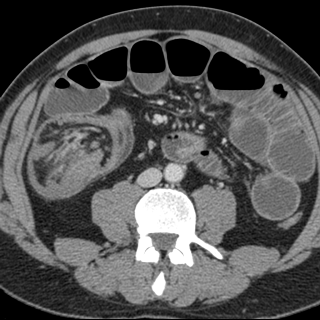

La CT scanner coronale

y avait le role importante dans diagnostic des

occlusion intestinale aigue :Y avait il de occlusion ? , la degree de occlusion ,

la situation de obstacle , la cause et les complications .

Aspect radiologique TDM de occclusion de l'intestin

grele est : |

| L'occlusion par bride et

adherence represente de 50% des occlusions

intestinales . Aspect TDM particuliairement est

image de bec des oiseaux ( fleche rouge ) au niveau

de l'obtacle . Image de distension de l'intestin sus

- lesionelle et image hydro-aerique transitionnel .

L'intestin sous -lesionelle est collabe totale |

Image TDM en coupe

sagitale : Occlusion de l'intestin aigue avec

signe de bec de oiseaux ( fleche rouge ) et

dilatation intestinale en amont et signe de feces (

retention de feces au niveau de l'intestin sus -lesionelle |